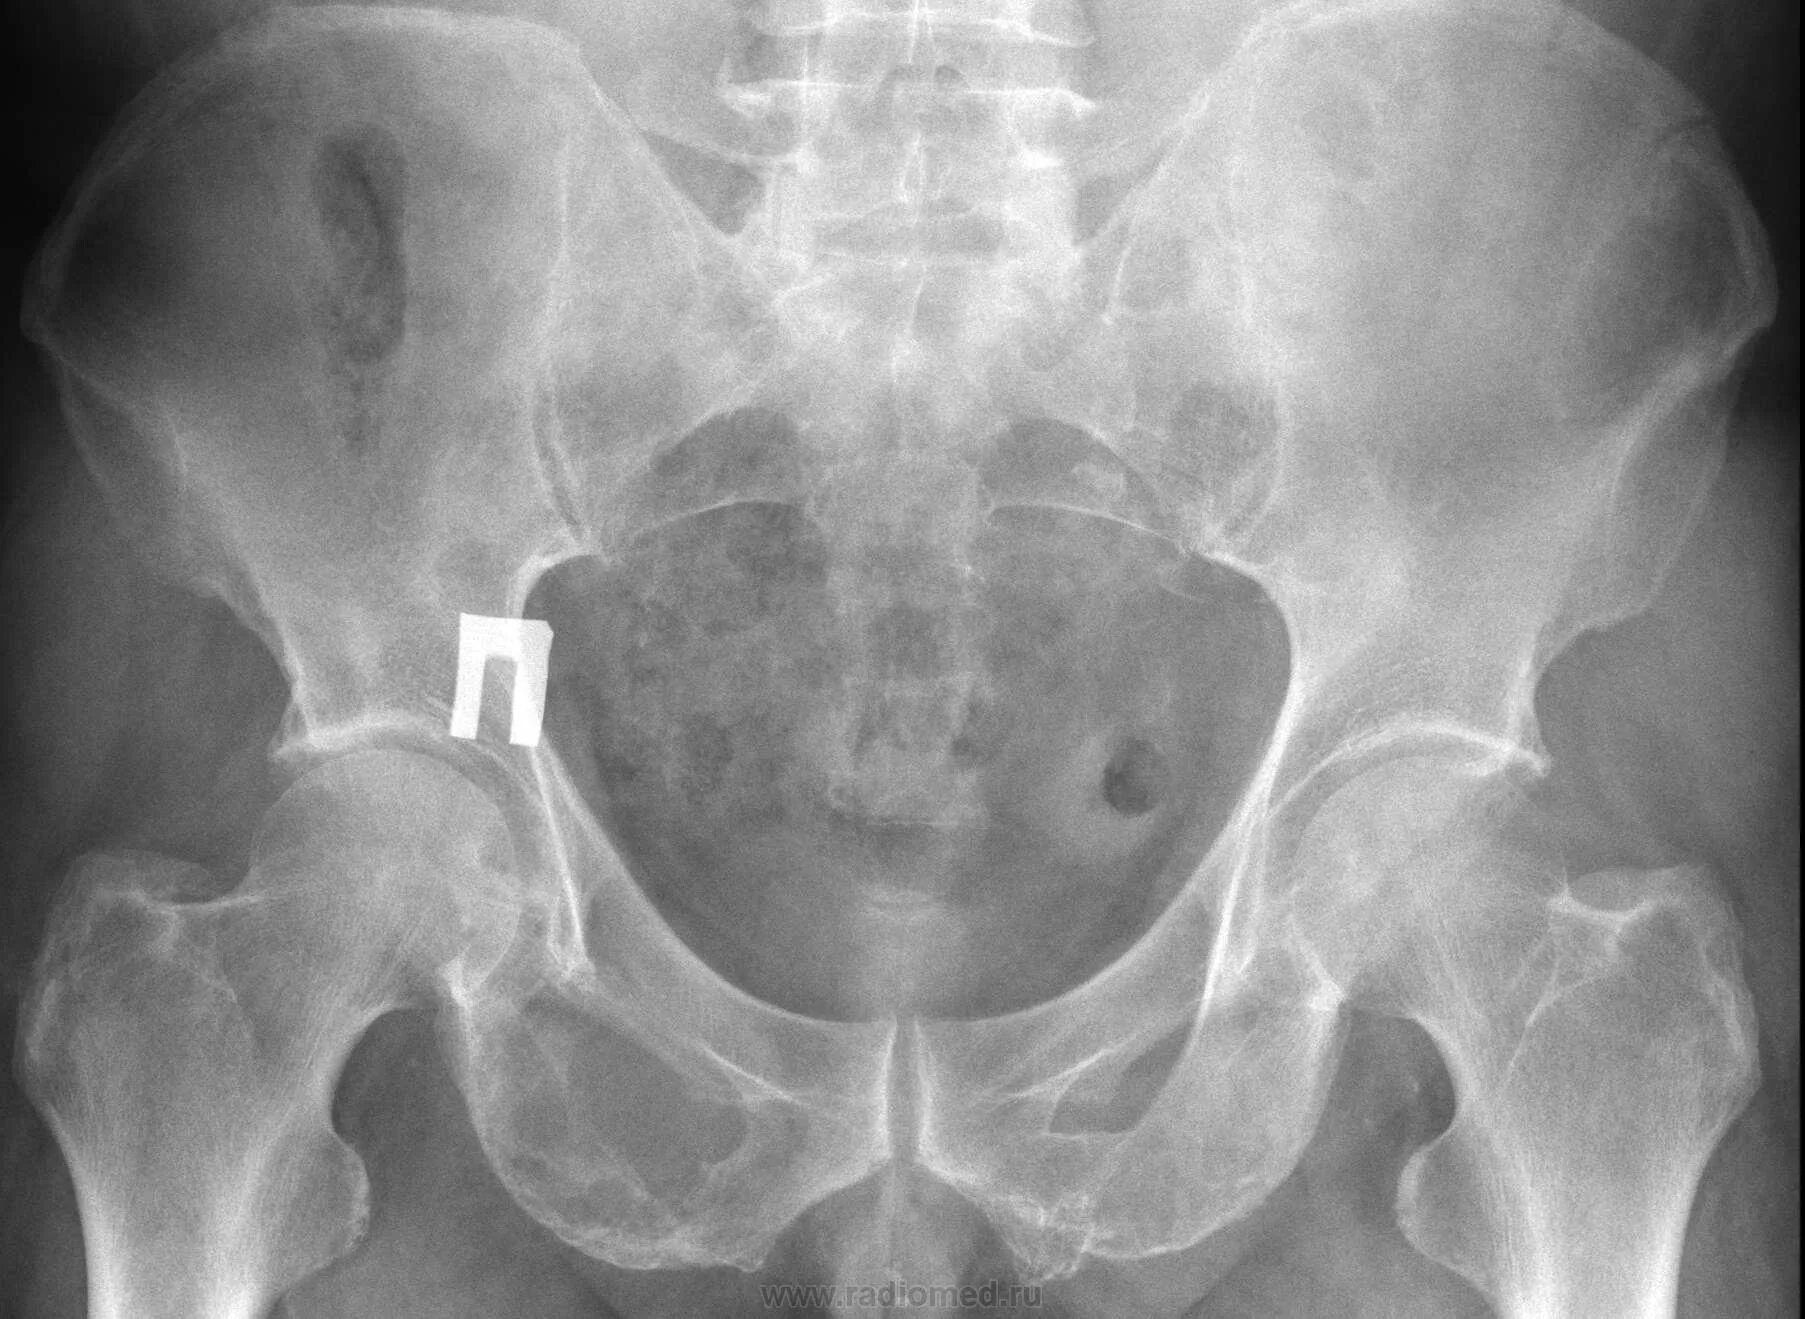

Метастазы в тазобедренном суставе